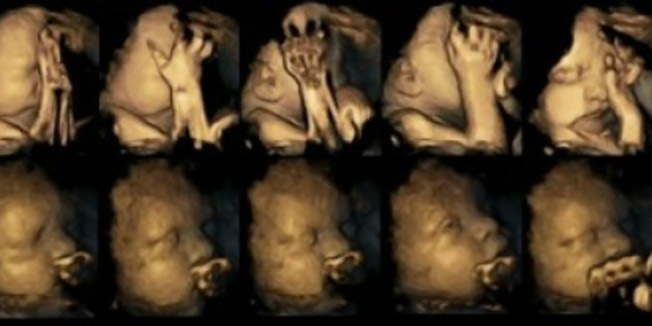

ALARMANTNE SNIMKE S ULTRAZVUKA Evo što se događa s fetusom kada majka za vrijeme trudnoće puši

Znanstvenici su, naime, uz pomoć ultrazvuka pokazali kako pušenje utječe na pokrete usta i ruku fetusa te kako sporije razvija njegov središnji živčani sustav.

Voditeljica studije, dr. Nadja Reissland s engleskog Durham sveučilišta, nada se kako će slike jednog dana biti iskorištene da pomognu majkama da donesu zdraviju odluku.

- Kada majkama pokažemo ovu video snimku fetusa, više će ih prestati pušiti - kazala je Reissland za AP.